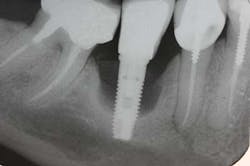

A 52-year-old woman with a noncontributory medical history, taking no medications with no reported food or drug allergies, was referred to my office from a general dentist in order to obtain a second opinion. She had a lower right premolar implant placed in an oral surgery office five years ago that was suffering from severe peri-implantitis. (Fig. 1) Her first dentist told her that the implant had to be removed and that her treatment options were a fixed partial denture in the form of a three-unit bridge or a partial denture because re-implantation was not feasible. In addition, he sent her to a periodontal office that verified his statement, telling the patient that because of nerve proximity and the poor chance of ridge augmentation, re-implantation was unlikely. When she asked if saving the implant was possible, both the dentist and the periodontist told the patient that because of the level of bone loss, regenerative treatment would not work.Fig. 4